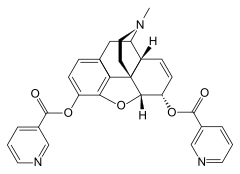

3,6-diesters of morphine

- Acetylpropionylmorphine

- 3,6-Dibutanoylmorphine

- Diacetyldihydromorphine (dihydroheroin, acetylmorphinol)

- Dibutyrylmorphine

- Dibenzoylmorphine (first designer drug)

- Diformylmorphine

- Dipropanoylmorphine

- Heroin (diacetylmorphine)

- Nicomorphine

Structures

| 3,6-diesters of morphine | ||||

|---|---|---|---|---|

Acetylpropionylmorphine Acetylpropionylmorphine |

3,6-Dibutanoylmorphine |  Diacetyldihydromorphine Diacetyldihydromorphine(dihydroheroin, acetylmorphinol) | ||

Dibutyrylmorphine Dibutyrylmorphine |

Dibenzoylmorphine Dibenzoylmorphine |

Diformylmorphine Diformylmorphine | ||

Dipropanoylmorphine Dipropanoylmorphine |

Heroin Heroin(diacetylmorphine) |

Nicomorphine Nicomorphine | ||